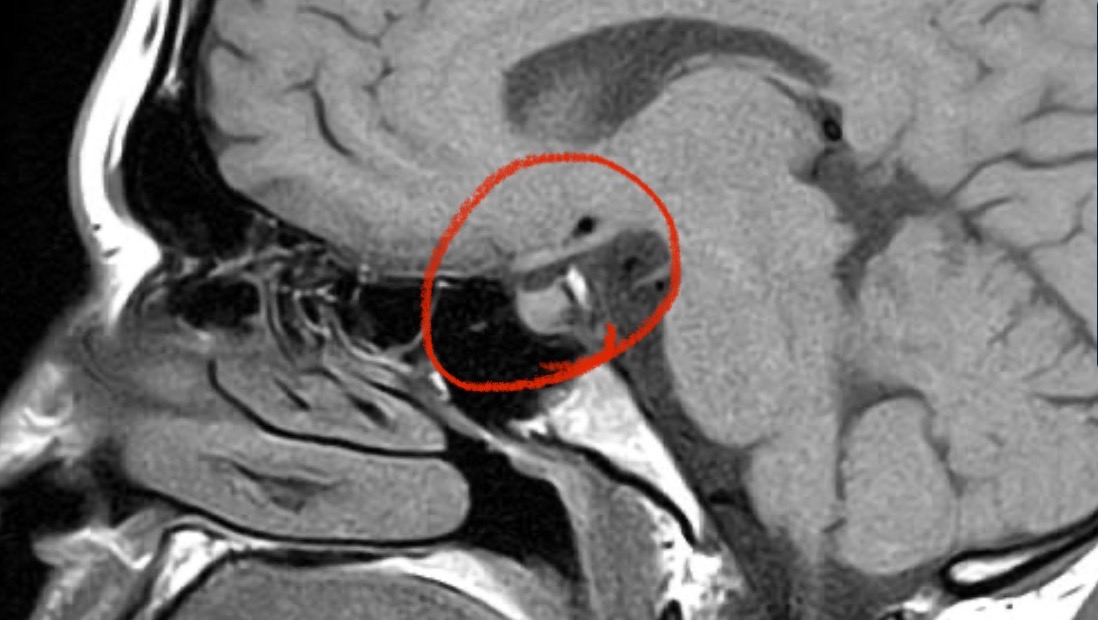

My name is Hannah Carrico, and in November 2024, my life changed when I was diagnosed with a benign brain tumor called a prolactinoma.

While I am incredibly grateful that it isn’t cancer, this diagnosis has still completely altered my life. My tumor has previously hemorrhaged in my brain, making it unstable and requiring urgent surgical intervention. Because of the complexity, I’ve already been passed between multiple neurosurgeons, and I am now scheduled for surgery at the Mayo Clinic in February.

This tumor doesn’t just exist on an MRI—it affects my hormones, vision, immune system, mental health, and fertility. It has impacted every part of my life.

I will be posting my MRI images below, not only to show the tumor but also to raise awareness for prolactinomas and invisible illnesses like mine.